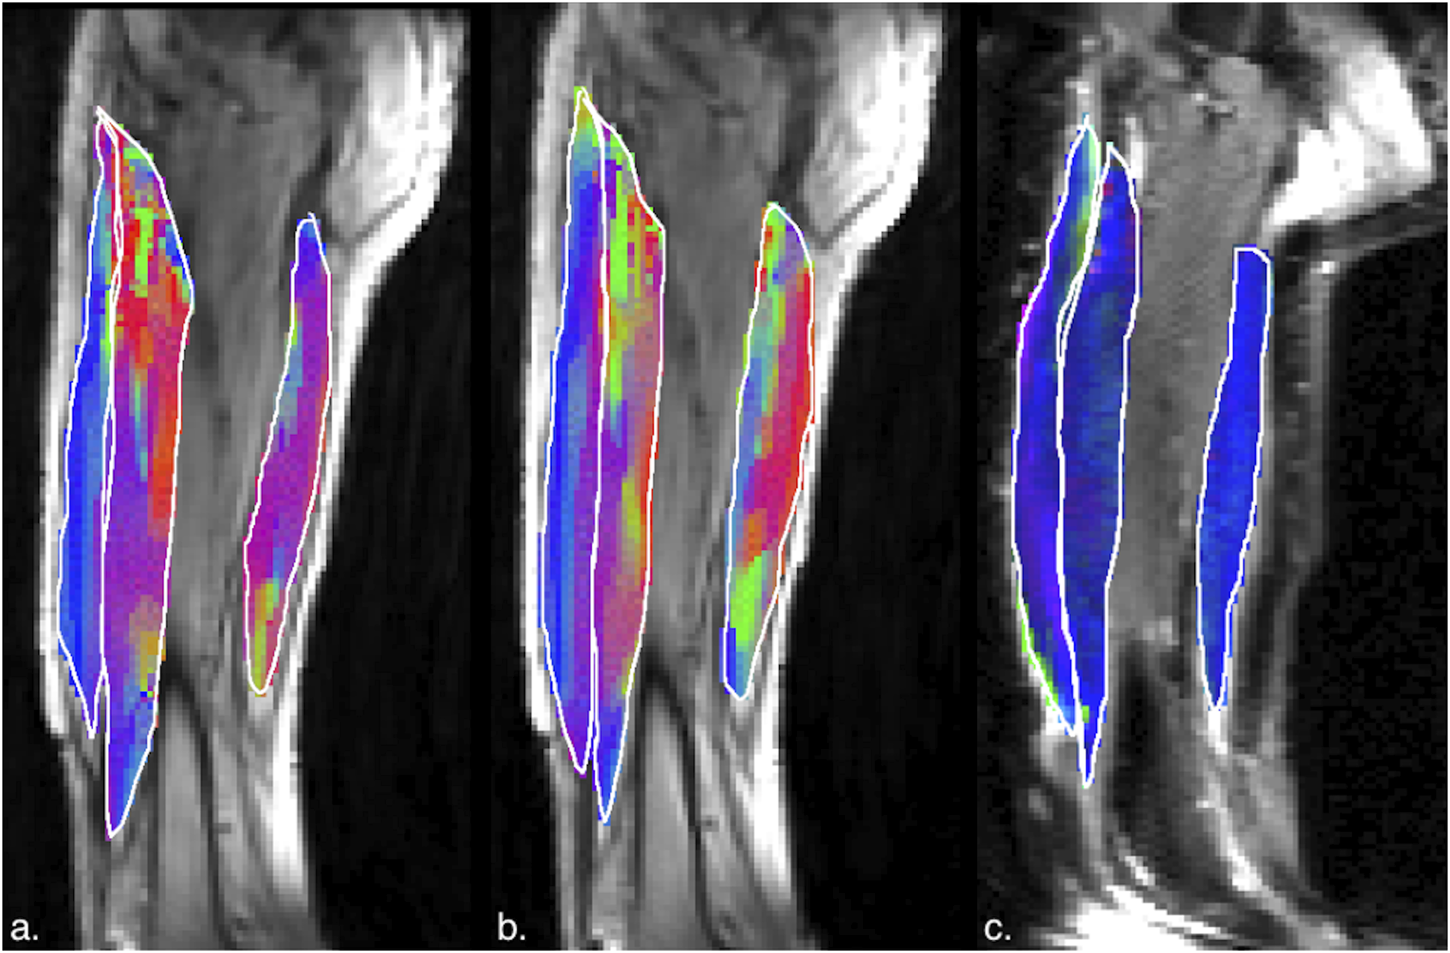

Figures 5, 6 are temporal plots of muscle kinematics extracted from ROIs placed in the VM muscle and LBF muscles respectively; plots are shown for one subject during isometric contraction at 30%MVC. Of note is that the velocity in the VM (quadriceps) and LBF (hamstring) are opposite in sign indicating the agonist-antagonist activation pattern. Figure 7a is the colormap derived from the eigenvector corresponding to the negative eigenvalue and is shown for one slice at the peak of the contraction cycle at 45% MVC; the colormaps are shown inside the contours of three muscles manually outlined in the magnitude image: from left to right in each image, the contours are VL, VI and LBF. Figure 7b is the colormap from the same slice and temporal frame (as Figure 7a) at 30% MVC. The colormap of the lead eigenvector of the diffusion tensor imaging (DTI) in a matching slice is shown in Figure 7c. It should be noted that the DTI suffers from susceptibility induced artifacts arising from the fact that these images were acquired with a large FOV in the sagittal plane to cover the length of the thigh. The muscles were manually contoured independently on the baseline image of the DTI and the colormaps are shown inside the contours of VL, VI and LBF muscles. The DTI colormap confirms that the fibers in the thigh are aligned predominantly in the superior-inferior direction. Figures 8a–c shows images arranged similarly to Figures 7a–c for the same subject but at a different anatomical location. The manual contours of the muscles in Figure 8 refer to the following from left to right: RF, VI and ST/SM muscles. Note the quadriceps muscles are labeled as ST/SM as the contoured muscle is possibly a mixture of both.

Figure 8. (a) Magnitude image with colormaps shown within manually outlined contours of the rectus femoris, vastus intermedius and the semitendinosus and semimembranosus muscles (from left to right). The colormap shows the eigenvector direction corresponding to the negative eigenvalue at the temporal frame at the peak of contraction at 45% MVC. The following color mapping scheme is used: red hue (x-component, Medial-Lateral), green hue (y-component, Anterior-Posterior), blue hue (z-component, Superior-Inferior). (b) Image similar to that show in (a) for the same anatomical location at 30%MVC effort. (c) Colormap of the lead eigenvector of the diffusion tensor imaging (DTI) at the location of the dynamic image with the same three muscles manually outlined. This colormap shows the direction of the muscle fibers.

The agonist/antagonist behavior can be seen in the temporal plots of the velocity where the velocity is positive in the quadriceps muscles in the contraction phase while it is negative in the hamstrings; the latter finding indicates that when the quadriceps are contracting, the hamstrings are lengthening (coactivation). It should be noted that the incompressibility of muscle tissue combined with transverse asymmetry of muscle deformation leads to a negative eigenvalue and a positive eigenvalue with nearly equal magnitudes at each voxel. When the muscle is contracting during the dynamic cycle, the direction of the negative eigenvalue (contraction) will be approximately along the fiber direction and the direction of the positive eigenvalue will be perpendicular to the fiber, i.e., in the fiber cross-section. The opposing action of the hamstrings to that of the quadriceps is seen in the colormaps of the eigenvectors corresponding to the compressive (negative) strain in the contraction phase of the dynamic cycle. The colormap of the negative strain eigenvector at contraction shows the VL and RF (quadriceps) muscles have a predominantly blue hue indicating the strain eigenvector is along the superior- inferior direction while the hamstring muscle (LBF and ST/SM) have a predominantly red hue (albeit with some heterogeneity) indicating the strain eigenvector is along the medial-lateral direction. This indicates that positive strain exists along the muscle fibers of the hamstrings (lengthening) during the contraction cycle when the quadriceps muscles are contracting. The VI muscle has a more heterogenous colormap at both anatomical locations. However, as visualized in the diffusion colormap, the VI fiber orientation has a blue to blue-green hue as one traverses from distal to proximal. This, combined with the fact that fibers are known to rotate on isometric contraction could potentially cause the strain colormaps to reflect the rotated fiber direction at the peak and not at the start of the contraction (time point at which the DTI was acquired). The extent of fiber rotation is also likely to be dependent on the muscle. Future work will be focused on reorientating the DTI derived eigenvectors using the displacements derived from the dynamic imaging to compute the fiber orientation at the peak of the contraction. It is acknowledged that the strain colormaps are noisy; this arises from the fact that noise is amplified when spatial gradients of displacements are computed to extract strain. Anisotropic diffusion filtering of the phase images as well as the colormaps served to reduce some of the noise; future work will be focused on further reducing noise. However, the fact that the colormap of the strain eigenvector is similar for 30% and 45% MVC indicates that these are consistent and robust determination of the orientation.